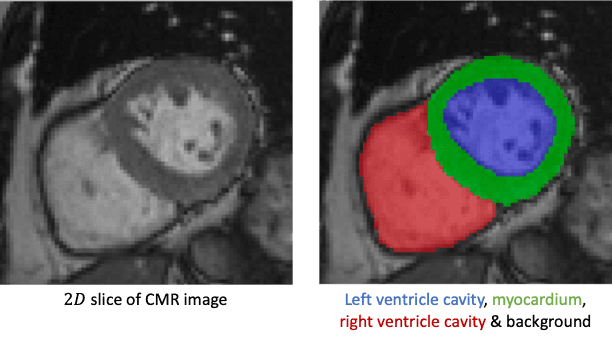

LVSegmenter: Left Ventricle Segmentation

Custom model for left ventricle segmentation in cardiac MRI. Based on a Kaggle-style challenge (IMA205: Apprentissage pour l'image et la reconnaissance d'objets).